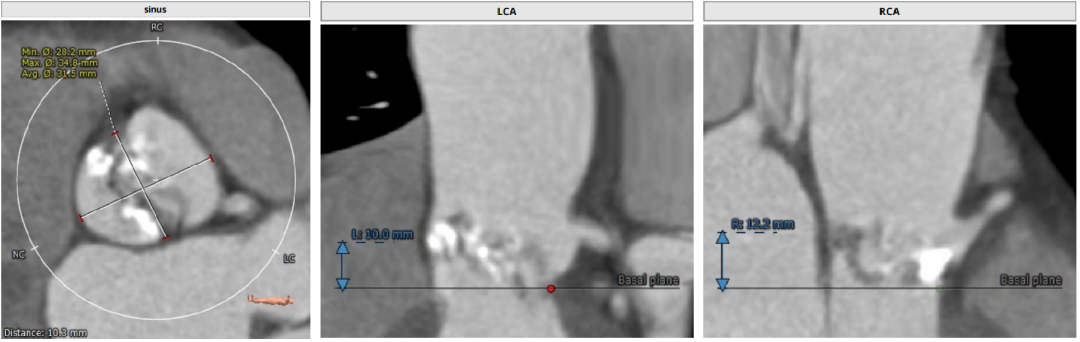

CT分析

Anulus 25.7、LVOT 23.7;STJ高度可,窦部空间足够;初步预估29/32瓣膜。

升主未见增宽,角度尚可,轻度钙化。

左右冠高度不低,球扩体位:LAO 26、CRA 18;释放体位:LAO 9、CRA 4;心室腔略小。

入路直径足够,分叉点足够高。右股作为主入路。